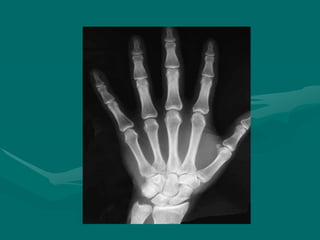

Bone Anatomy

• Total of 27 bones in hand and wrist.

• These are grouped into carpals, metacarpals,

and phalanges.